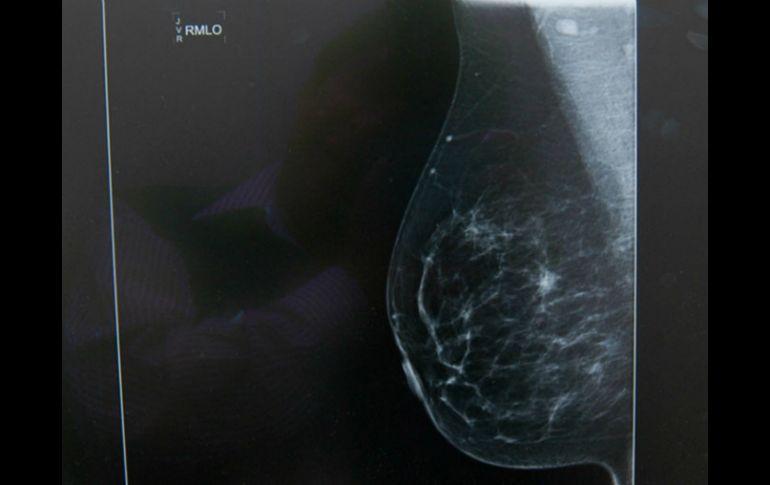

Tecnología | El descubrimiento podría abrir nuevas opciones terapéuticas para combatirlo Los tumores de mama necesitan suministro de grasa para crecer El descubrimiento podría abrir nuevas opciones terapéuticas para combatirlo Por: EFE 5 de abril de 2016 - 10:08 hs Se ha puesto al descubierto la necesidad de las células tumorales de importar lípidos externos. NTX / ARCHIVO BARCELONA, ESPAÑA (05/ABR/2016).- El cáncer de mama necesita grasa exterior para crecer, lo que podría abrir nuevas opciones terapéuticas para combatirlo, según un estudio de un equipo español de científicos que publica Nature Communications. El equipo, liderado por el Instituto de Investigación Biomédica (IRB) de Barcelona en colaboración con hospitales españoles y la Universidad Rovira i Virgili (URV), descubrió que las células de mama tumorales necesitan recoger grasas del exterior y trasladarlas a su interior para poder seguir proliferando. La principal proteína en este proceso es LIPG, una enzima localizada en la membrana que envuelve las células sin cuya actividad la célula tumoral no puede crecer. Los análisis de más de 500 muestras clínicas de pacientes con distintos tipos de tumores de mama revelan que el 85 % tienen altos niveles de LIPG. Según cifras de la Organización Mundial de la Salud, en el mundo se diagnostican 1.38 millones de nuevos casos y produce 458 mil muertes al año. Hasta ahora, los investigadores conocían que las células tumorales para crecer captan glucosa del exterior igual que sabían que reprograman su maquinaria interna para producir muchos más lípidos (grasas). La novedad del descubrimiento radica en que, por primera vez, han puesto al descubierto la necesidad de las células tumorales de importar lípidos externos. "Este nuevo conocimiento relacionado con el metabolismo podría representar un talón de Aquiles para el cáncer de mama", explicó el jefe de grupo del IRB Barcelona, Roger Gomis, co-líder del trabajo junto a Joan J. Guinovart, director del IRB y catedrático de la Universidad de Barcelona. Los científicos demostraron en modelos animales y en células tumorales que bloqueando la actividad de la LIPG el tumor deja de crecer. "Lo prometedor de esta nueva diana terapéutica es que la función de la proteína LIPG no parece ser indispensable para la vida, por lo cual su inhibición generaría menos efectos adversos que otros tratamientos", puntualizó el primer firmante del trabajo, Felipe Slebe. Guinovart precisó que, "al ser una proteína de membrana, es potencialmente más fácil conseguir una molécula farmacológica para bloquear su actividad". LIPG tiene "muchas virtudes" como diana, aseguró Gomis, ya que "de prosperar una substancia que la anulara podría convertirse en la base de una quimioterapia más eficaz, pero menos tóxica que las actualmente". Los científicos están buscando ahora alianzas internacionales para desarrollar inhibidores para LIPG. Temas Descubrimientos ciencia Ciencia médica Células Cáncer de mama Calor de hogar Lee También Lugares donde hacen la mastografía gratis en CDMX y Edomex Estudio chino revela una mutación que eleva riesgo de alzhéimer Entrevista: Gerardo Cárdenas muestra “Lo que no se ve” Sociales: El Eco de lo Invisible, una exposición fotográfica sobre las huellas ocultas del cáncer Recibe las últimas noticias en tu e-mail Todo lo que necesitas saber para comenzar tu día Registrarse implica aceptar los Términos y Condiciones